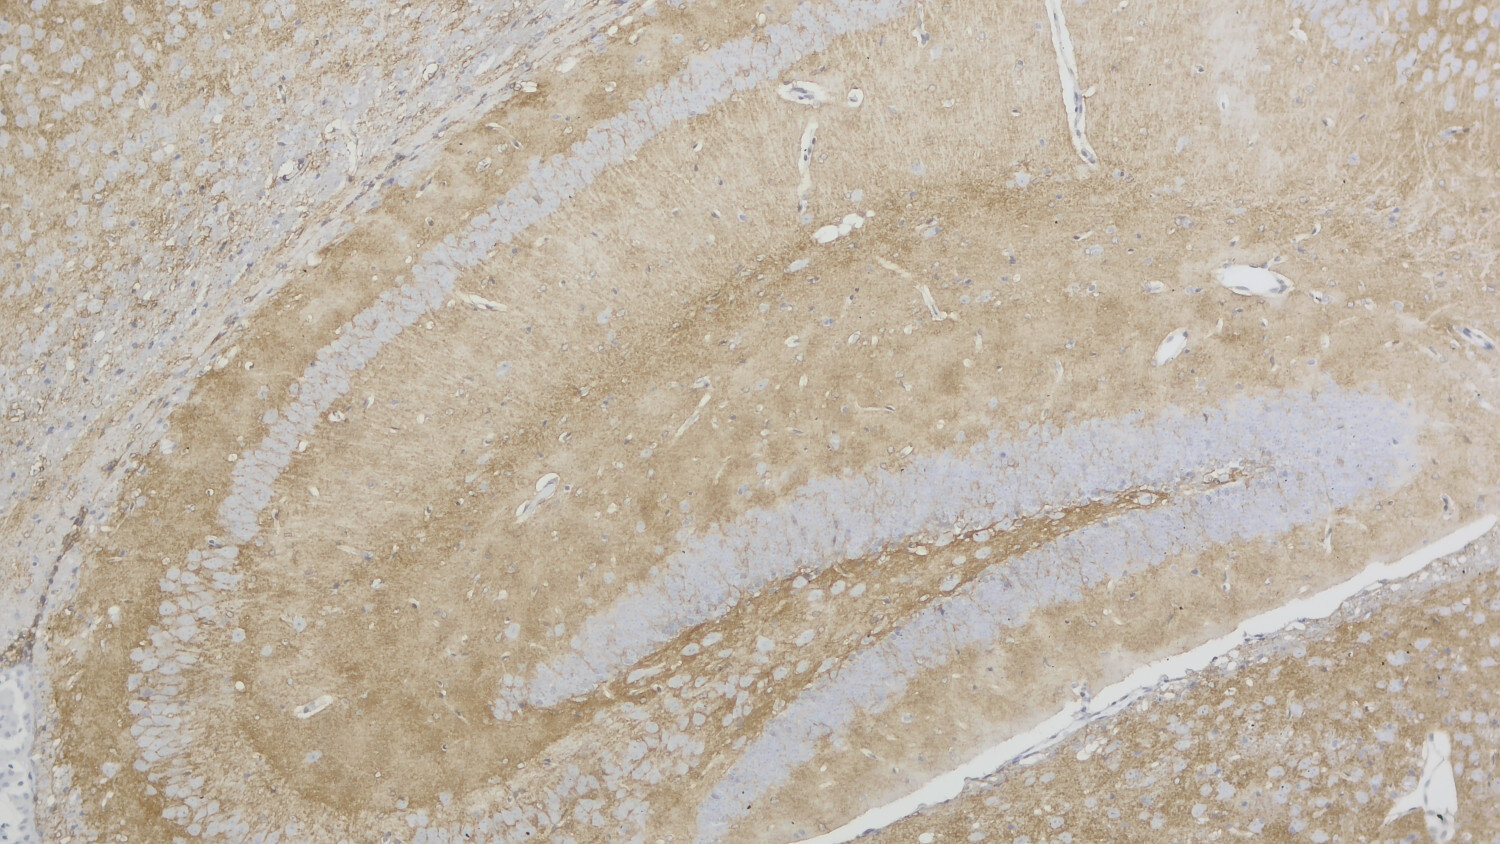

IHC: 1 : 500 gallery

IHC-P (FFPE): 1 : 500 gallery

Immunohistochemistry (IHC-P) of formalin fixed, paraffin embedded (FFPE) tissue (some antibodies require special antigen retrieval steps, please refer to the ”Remarks” section). Immunoreactivity is usually revealed by fluorescence or a chromogenic substrate.